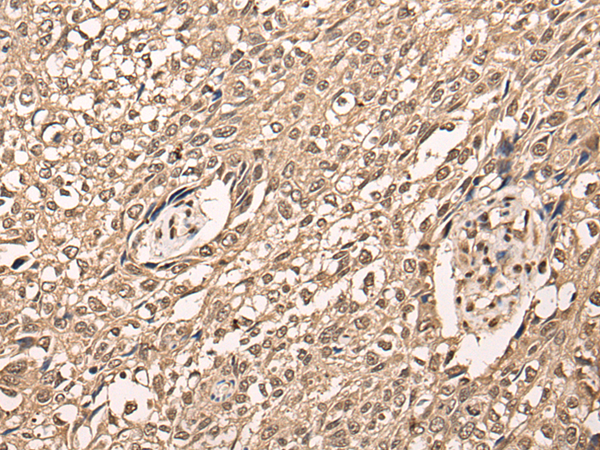

ELISA, IHC |

IHC positive control: |

Human lung cancer and human colorectal cancer |